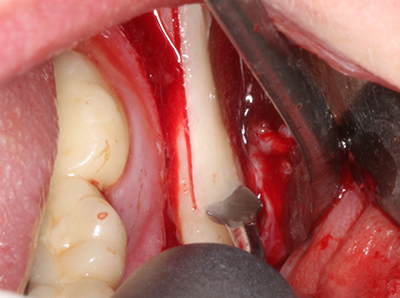

El tejido óseo no solo tiene un contenido puramente mineral, sino que también presenta una importante proporción de fibras de colágeno. Esto no solo garantiza una buena resistencia a la presión, sino también una cierta flexibilidad, que puede aprovecharse para la realización de aumentos. En la plastia de expansión clásica a efectos de una partición ósea, la cresta maxilar atrofiada se divide en su eje longitudinal y, tras alcanzar una profundidad de osteotomía suficiente, se extiende con cuidado (fig. 13-16), en un caso ideal sin desperiostizar de forma visible el maxilar (Brugnami, Caiazzo et al. 2014, Stricker, Fleiner et al. 2014). Los sistemas de tornillos y placas con distancia de expansión creciente han demostrado su eficacia para distanciar entre sí las dos tablas óseas por debajo del umbral de rotura. Por regla general, se requieren anchuras de hueso residual de al menos 3 a 4 mm (Chiapasco, Zaniboni et al. 2006) para garantizar una flexibilidad y una cobertura ósea suficientes de los implantes que van a incorporarse. En caso necesario, una osteotomía de descarga vertical unilateral o bilateral puede mejorar la flexibilidad. Como alternativa a la técnica clásica se ha descrito una combinación con otras técnicas de aumento, sobre todo en la parte bucal.

Con el uso de sierras piezoeléctricas la división se efectúa de forma especialmente cuidadosa y sin pérdidas importantes de las dimensiones, por lo que no se han encontrado diferencias significativas entre los implantes realizados en el maxilar dividido y en la cresta alveolar no deficitaria (Chiapasco, Zaniboni et al. 2006, Danza, Guidi et al. 2009). No obstante, precisamente en la partición profunda y limitada de forma local, es preciso asegurarse de que exista una adecuada irrigación por agua para evitar que se produzcan sobrecargas térmicas en las áreas de osteotomía apical.

Fig. 13: En este paciente de 52 años con una anchura del hueso residual del maxilar inferior de 4 mm, hay que asegurarse de que exista refrigeración por agua adecuada durante la partición del hueso.

Fig. 14: Incorporación de cuatro implantes RSX cónicos (Bego Implant Systems, Bremen).